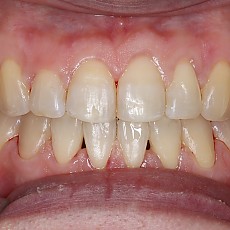

시술전후사진 6 페이지

Total 189건 6 페이지